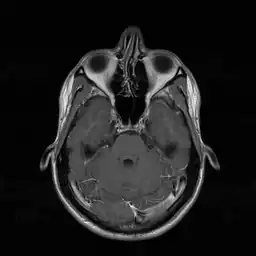

In de neusholte zelf bevinden zich aan weerszijden symmetrisch drie dunne, met slijmvlies beklede botplaten (conchae of neusschelpen), die het inwendige oppervlak van de neusholte sterk vergroten. Deze plooien vangen de kleinere deeltjes die in de ingeademde lucht aanwezig zijn op. Ze zijn goed doorbloed en verwarmen zo de ingeademde lucht, zodat deze op lichaamstemperatuur komt. Ook zorgen ze voor een zekere turbulentie in de luchtstroom zodat geurstoffen worden getransporteerd naar het reukslijmvlies. Dit slijmvlies bevindt zich boven in de neusholte, onder de schedelbasis en tussen de oogkassen.

De linker- en rechterneusholte zijn van elkaar gescheiden door het neustussenschot of neusseptum, dat bestaat uit een voorste deel van kraakbeen en een achterste gedeelte van bot. In het slijmvlies van het tussenschot lopen veel oppervlakkige bloedvaatjes en de meeste neusbloedingen vinden hier hun oorsprong. De vaatkluwen in het slijmvlies van het onderste deel van het neusseptum, locus Kiesselbachi, vormt een predilectieplaats voor neusbloedingen.

In de neusholte draineren twee andere organen, de bijholten en de traanklieren.

Aan de laterale zijden draineert de kaakholte (sinus maxillaris). Boven in de neusholte draineren de voorhoofdsholte (sinus frontalis) en de zeefbeenholtes (sinus ethmoidici).